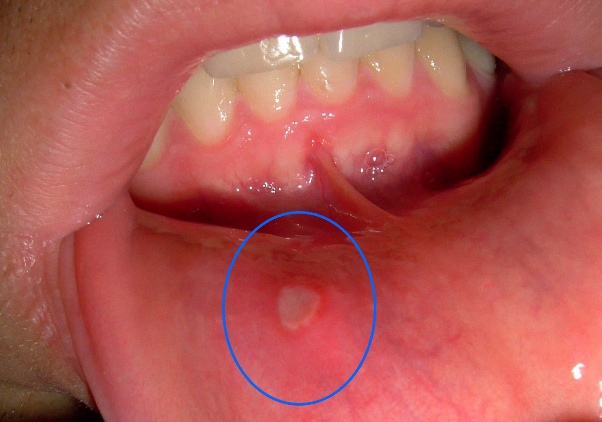

Afte su zapravo male ulceracije koje se javljaju na unutrašnjim dijelovima usana, jeziku ili na sluznici usne šupljine.

Iako su najčešće bezopasne, mogu izazvati bol koja otežava svakodnevne aktivnosti. U ovom članku ćemo vas upoznati s nekoliko prirodnih tretmana koji mogu pomoći u ublažavanju simptoma i ubrzanju procesa zacjeljivanja.